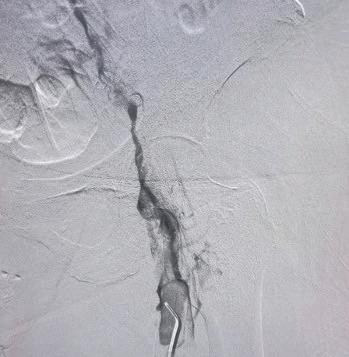

Pre-procedural venogram shows the extent of thrombus burden (1); postClotTriever venogram (2); thrombus extracted (3); pre-procedural IVUS shows extent of thrombus (4); and post-procedural IVUS demonstrates complete thrombus removal (5)

A woman in her early 60s presented with right leg pain and swelling. An ultrasound revealed unilateral right iliofemoral DVT, and the decision to intervene using the ClotTriever BOLD Catheter was made.

Procedural overview

The right popliteal vein was accessed with a micropuncture needle and wire under ultrasound guidance, and exchanged for a microsheath, ultimately upsizing to a short 10F sheath. A venogram demonstrated significant thrombus within the femoropopliteal segment, common femoral vein and extending into the external iliac vein. The lesion was crossed into the inferior vena cava (IVC). Next, pullback intravascular ultrasound (IVUS) from the IVC to the access site was performed to identify the extent of thrombus. A glidewire was advanced up into the right subclavian vein, and a vertebral catheter was advanced over it. Next, the glidewire was exchanged for a guidewire 7cm tip. A 19F dilator was used, followed by insertion of the ClotTriever sheath. The funnel was deployed under fluoroscopic guidance and the ClotTriever BOLD Catheter was advanced into the popliteal vein. The nitinol coring element and mesh collection bag were then deployed at the iliac vein, and the catheter was then retracted, capturing and removing significant acute thrombus. In total, four ClotTriever BOLD passes were completed. Completion IVUS showed complete thrombus removal. Completion venogram demonstrated brisk cephalad flow. Total procedure time was 35 minutes, while total device time was 10 minutes. There was estimated total blood loss of 20ml.

Conclusion

The patient’s pain resolved immediately postprocedure, with the swelling improving greatly. In followup, the swelling was resolved and the patient is doing well.